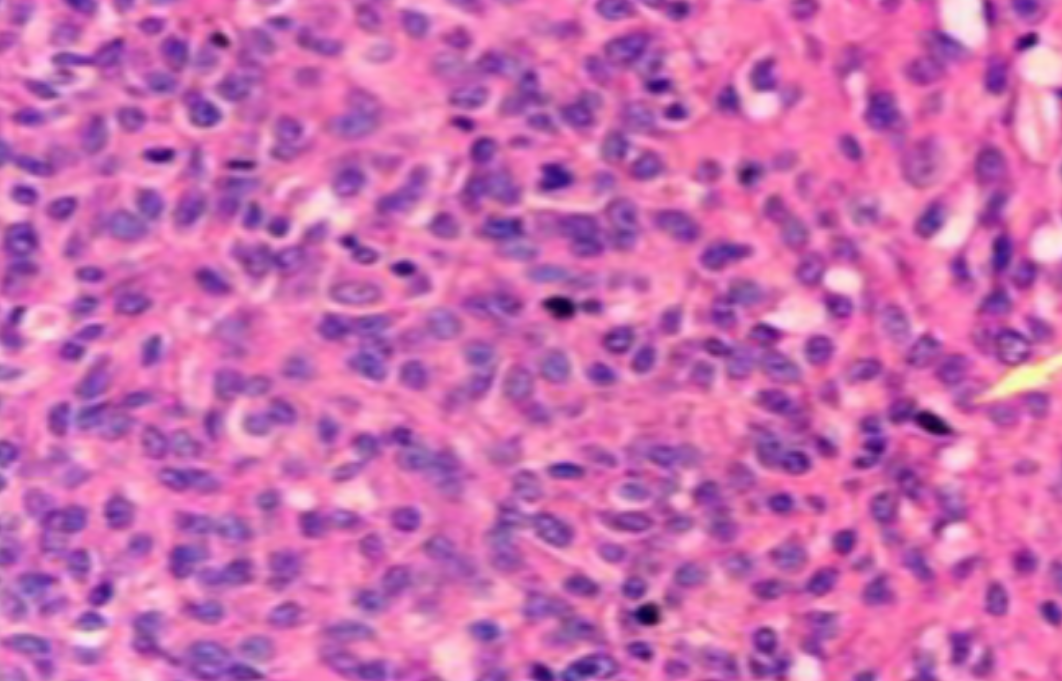

HE染色,全称苏木精-伊红染色法(Hematoxylin and Eosin staining),是最常见的组织切片染色技术之一,用于在显微镜下观察和分析组织或细胞的结构和形态。

虽然HE染色是最常见且最基础的染色技术之一,😭但在实验过程中,很容易出现各种情况导致染色切片质量参差不齐。所以,小编根据以往实验经验,给大家整理归纳出了15个HE染色中的常见问题,还包含问题原因分析以及解决方法哦~

形成原因:切片经梯度乙醇处理后没有完全脱水,导致二甲苯透明、中性树胶封固后残留大量水分。 解决方法:首先移去盖玻片,用二甲苯溶解封固剂如中性树胶,再将切片置入无水乙醇内,待切片重新脱水完全后,用二甲苯透明处理,中性树胶封固。要注意所有用于脱水和透明的液体,在使用一定时间后,应及时更换。 二、细胞核呈红、棕色 形成原因:苏木精染色液过度氧化,切片在苏木精染液染色后返蓝不足。 解决方法:每次染色之前检查苏木精染色液的染色能力,发现苏木精染色液氧化过度应及时更换。此外,切片经苏木精染色后,要给切片以足够的蓝化时间,蓝化过程可用流水、温水、弱碱性溶液(如稀氨水或0.2%碳酸氢钠)等处理。 三、切片在脱蜡后出现大片白色斑点 形成原因:由于烤(烘)片温度太低,切片上的组织蜡膜在脱蜡前没有充分烤(烘)融化。或是因为切片在二甲苯液中停留时间不足,或二甲苯使用过久,造成的脱蜡不彻底。 解决方法:若是由于切片烤(烘)温度低所致,可以先用二甲苯去除切片上的封固胶,然后重新用二甲苯脱去切片上的石蜡,再进行后续染色。若是由于切片在脱蜡的二甲苯中停留时间不足或脱蜡二甲苯使用过久浓度不足所致,则需将切片退回到二甲苯中,停留较长时间,或更换二甲苯液体重新脱蜡,再入乙醇重新脱二甲苯,入0.5%盐酸水溶液褪色后,重新HE染色。 四、细胞核苍白暗淡,即苏木精染色太淡 形成原因:切片在苏木精染色液停留时间太短;苏木精染色液过度氧化,失去染色能力,不能再继续使用;分化步骤处理时间过长;固定不及时。此外值得注意的是,若骨组织细胞核暗淡,大多是脱钙过度造成的。 解决方法:切片重新染色。如果组织在酸性固定液(如Zenker、Bouin)或非中性缓冲甲醛液固定时间过长,细胞核染色能力将减弱,需增加其在苏木精染色液的时间,或用一些方法增加组织的嗜碱性,以改善细胞核的着色。例如,上述组织玻片可以使用Weigert铁苏木精染色液。如果组织是用Zenker液固定的,可将切片脱蜡后放在5%碳酸氢钠溶液3~4h,流水冲洗5min后染色。如果组织是用Bouin液固定的,可将切片脱蜡后放在5%碳酸锂1h,流水冲洗10min后染色。 五、细胞核过染,苏木精染液占据了细胞质 形成原因:玻片在苏木精染色液停留时间过长,或是切片太厚、分化步骤时间太短。 解决方法:如果不是因为切片太厚(用显微镜仔细上下微调,只有一二层细胞核层次),就需将切片进行脱色、漂白、重新染色,适当调整染色和分化时间。但如果确定是由于切片太厚导致的细胞核过染,则需要重新切片。 六、伊红着色淡 形成原因:可能是伊红染液pH值大于5,也可能是蓝化液残留过多,切片太薄,或是切片经伊红染色后在乙醇脱水时间过长。 解决方法:检查伊红染液pH值,必要的话,用乙酸将其调节在4.6~5.0之间,从而使伊红染色色彩艳丽。此外,确保每次蓝化步骤完成后,使用的弱碱性溶液被充分洗去,玻片上没有残留的弱碱性溶液。最后,检查切片的厚度,且脱水时不要让切片在低浓度乙醇中停留时间过长,因为含水多的低浓度乙醇会将切片伊红的颜色分化掉。 七、细胞质过染、分色不足 形成原因:伊红染色液浓度太高,特别是存在焰红燃料、四溴四氯荧光素钠。切片在伊红染色时间过长,或是切片在伊红染色后经乙醇脱水步骤时时间太短,而使乙醇分化伊红的作用不能产生,都能够使细胞质过染。 解决方法:适当稀释伊红染色液,减少伊红染色时间,或使切片在乙醇脱水等步骤时,停留时间相对均匀。同样,也要检查切片的厚度是否合适。 八、切片中出现蓝黑色沉淀物 形成原因:苏木精染色液中的金属膜黏附在玻片上。 解决方法:染色前仔细过滤苏木精染色液,建议使用半氧化苏木精染色液,如Gill苏木精染色液,可以避免过多的金属膜产生。 九、光镜下切片某些区域难以聚焦 形成原因:盖玻片上可能有封固切片的封固剂。 解决方法:移去盖玻片,重新用干净的盖玻片封片。检查切片封片方法,是人工手工封法,还是机器自动封法,如有问题及时调整。 十、封固剂从盖玻片与载玻片之间的缝隙回缩 形成原因:盖玻片弯曲或不平整,或是封固剂含二甲苯过多,稀释过度。 解决方法:移去盖玻片,重新找一张盖玻片,用干净的封固剂封片。如用手工封片法,保证在封固结束时,封固剂容器盖子为紧闭状态。且尽量使用小的容器盛装封固剂,一旦封固剂太黏稠,就可以选择废弃。 十一、细胞核呈灰蓝状态 形成原因:可能由于组织处理温度过高、过热,在液体石蜡中停留的时间过长。或是固定时间太短后,直接在高浓度的乙醇中进行了脱水处理。 解决方法:理论上来说,仅在组织浸蜡步骤才进行加热,组织不能在热蜡液中停留太久。如果由于某些原因不能进行下一步包埋处理,可将组织连同塑料包埋盒一并放置在室温空气中,冷却凝固,以备包埋。待需要包埋时再重新加温直至石蜡融化即可。组织在处理前必须确保固定良好,脱水最好能从低浓度的乙醇开始。 十二、类色素的点状结晶和黑色光滑细胞核 形成原因:这种裸核改变是因为切片封片前放置在空气中的时间太长,以至于二甲苯挥发,切片干燥。 解决方法:移去组织切片上的盖玻片和封固剂,重新处理。将切片水洗数分钟,然后重新脱水、透明、封固。封片过程中要保持组织切片的轻度湿润,尽量不要让其干燥。 十三、染色过淡或过浓 解决方法:如果染色过淡,可以增加染色剂的浓度、延长染色时间或更换新鲜的染色剂;如果染色过浓,则应减少染色剂的浓度或缩短染色时间。 十四、切片出现叠加褶皱 形成原因:新购买的玻片洁净度不够、用镊子撑开切片时操作不够熟练未能平整伸展,或玻片表面有油脂,切片粘贴不牢。另外,烤片时间不足、烤片温度过低或切片过厚造成切片脱落,都会造成重叠或有皱褶的情况。 解决方法:新购买的玻片最好能用硫酸清洁液浸泡一晚,然后流水冲洗干净。在适宜的温度下烤片时间宁长勿短,保证有充足的烤片时间和温度。另外,切片刀要锋利,才能切出厚薄适宜的切片,保证切片不会因为过厚而脱落。 十五、组织残缺不全或有刮划痕迹 形成原因:组织残缺不全是由于切片时修整蜡块时深度不够、组织没有全部暴露于切面。切片的刮划痕迹是由于切片刀的刀锋有缺口、包埋的组织有异物,或是钙化组织、骨组织及包埋石蜡有沙粒造成的。 解决方法:修整蜡块时保证组织块全部暴露于切面,切片时保证切片刀的锋利没刀口。同时在组织取材时去除手术异物和钙化组织。最后,骨组织要完全脱钙,这样可以保证切片的完整和平整美观。 *注:由于实验中导致结果出现误差的原因多种多样,以上内容仅供参考,具体根据实际情况进行判断。